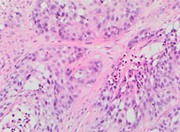

Invasive ductal carcinoma of the breast with clear cell and pseudo-lactating changes

Christopher Ovanez and others

Journal of Surgical Case Reports, Volume 2014, Issue 7, July 2014, rju063, https://doi.org/10.1093/jscr/rju063